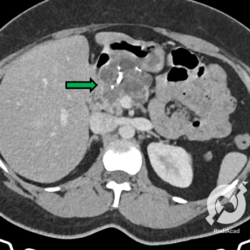

Assim como outras facomatoses, a doença de VHL também promove mutações em genes supressores tumorais, portanto neoplasias são frequentes. Neste paciente observamos uma grande lesão expansiva na loja da adrenal esquerda, de contornos regulares e atenuação heterogênea, apresentando componentes de partes moles e liquefeitos, bem como com calcificações de permeio. Com estas características pensamos em feocromocitoma de adrenal, tumor frequente na doença de VHL.